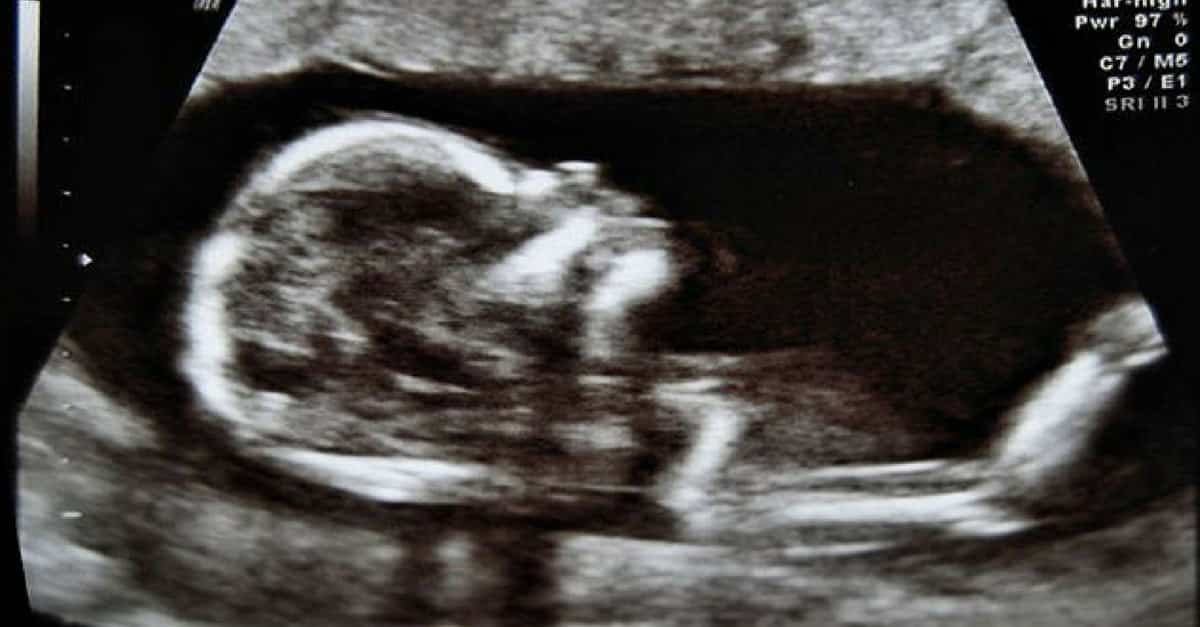

Para llegar a estos primeros híbridos humanos-animales, los científicos inyectaron células humanas en un embrión de cerdo y se desarrollaron junto con el embrión hasta la edad de 4 semanas, tiempo necesario para demostrar la efectividad de esta etapa del proyecto.

Como resultado, lograron 186 embriones híbridos sobrevivientes, con cerca 100.000 células humanas en cada uno.